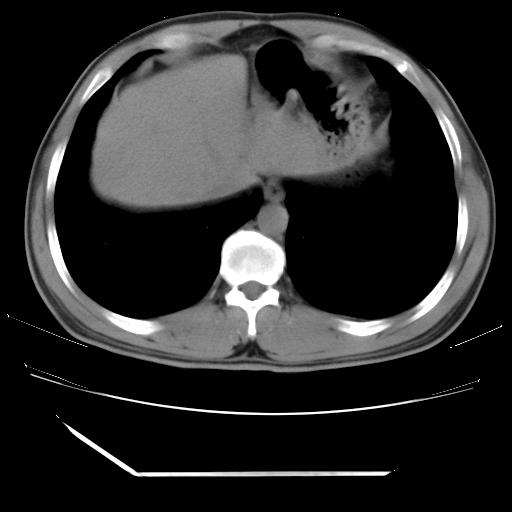

男,38岁,于2009年8月9日晚突发左侧胸痛,今x线提示左下肺阴影,为了明显确诊断,行ct检查,

左肺舌叶病变。主体病灶呈类圆形中心密度低,成液化趋势周边班片影分布

考虑肺脓肿

肺梗塞不能除外

虽然实验室检查支持炎性病变,且病变内有坏死改变(中央呈大片状低密度影),但仍不能掉以轻心,鳞癌也可以有这种影像改变。